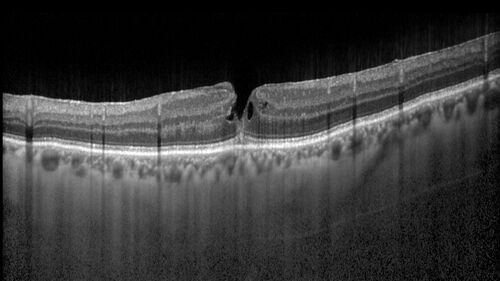

Lamellar Macular Hole - Evoluation over 5 years

65 year old man with Sturge weber and a choroidal hemangioma in the left eye. (See other images under sturge weber on this website). Has ongoing problem with his left eye. Now with Blurred vision in the right eye gradually worse the last few weeks. He has had a vitrectomy in the right eye 4 years ago for floaters. Laser for tears and cryo in the right eye 5 years ago. He is on Dorzolamide and Lumigan for glaucoma.

VA 20/32 OD, 20/40 OS

IOP 23 OD, 19 OS